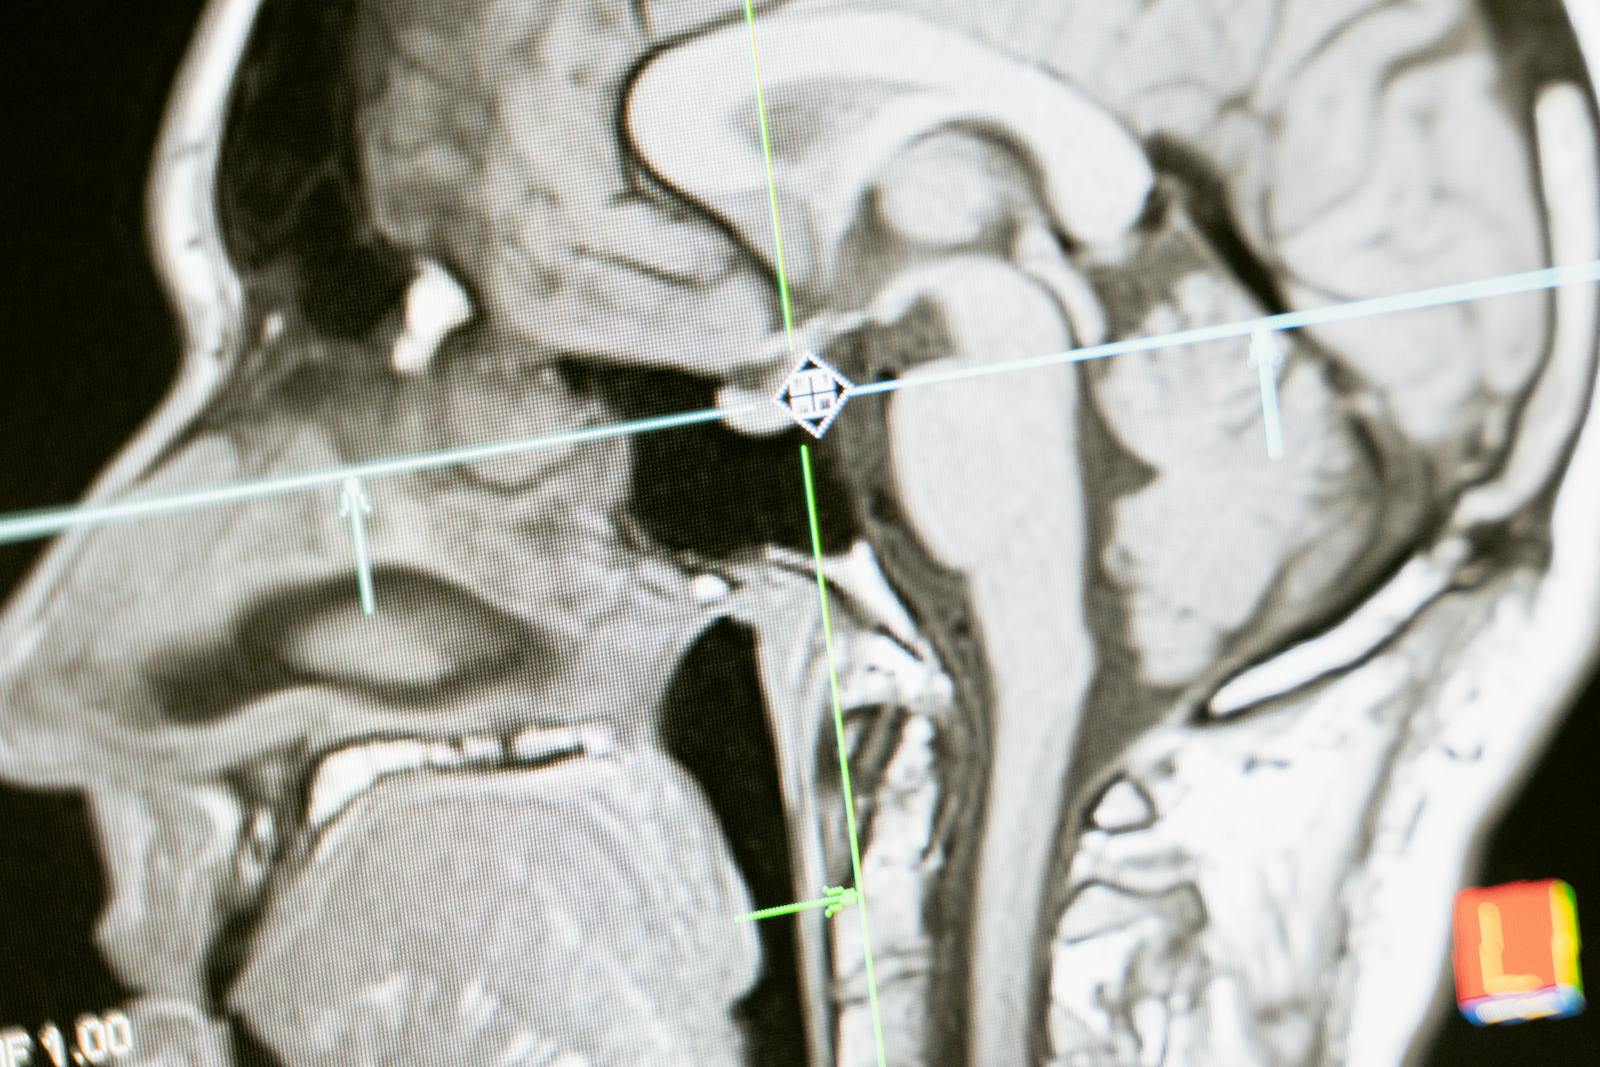

Research examining pregnant women scanned the brains of women before, during, and after pregnancy using multiple MRI scans, alongside women who had never been pregnant as a comparison group. The results reveal that grey matter decreased during pregnancy.

Not all brain regions changed equally. The most pronounced and persistent grey matter changes occurred in the default mode network — a brain system involved in self-perception, empathy, and altruism.